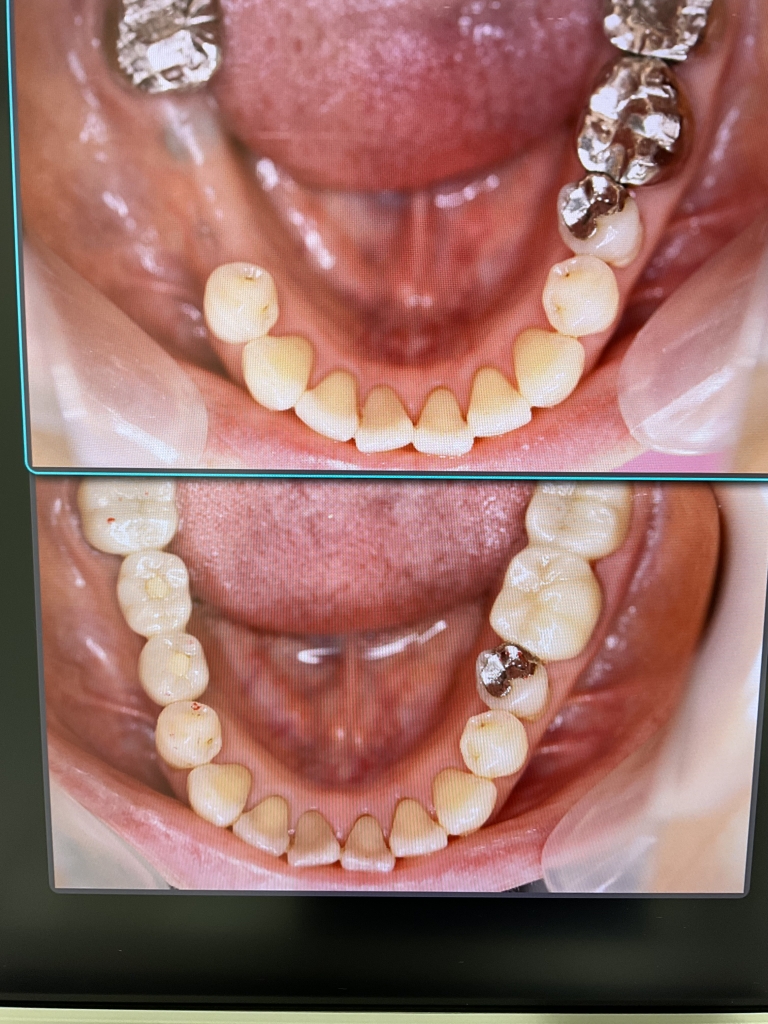

いつまでも健康的で若々しく、素敵な笑顔でいられるために、入れ歯や欠損などでお困りの患者さんにインプラント治療をお勧めします。

患者さんが安心して手術を受けていただけるように、CT撮影などの術前検査と十分なカウンセリングを行います。

万が一インプラント治療が適さない症例であれば他の治療法を提案させていただくこともあります。